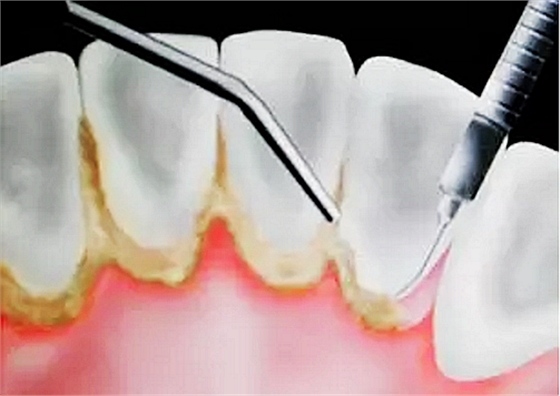

當(dāng)牙齦下存在的牙結(jié)石,或有牙槽骨吸收跡象時(shí),常規(guī)潔牙往往無(wú)法清除牙齦下的結(jié)石,此時(shí)需要進(jìn)行牙周刮治了。

![U7FZD~BYN9(C]S_P$Q_V)4R.png U7FZD~BYN9(C]S_P$Q_V)4R.png](/Mobile/UploadFiles/FCK/2017-06/6363253152156700223823897.png_280.jpg)

牙槽骨一旦吸收很難再生,所以,牙周刮治的目的是為了防止進(jìn)一步的牙槽骨吸收,牙周袋形成以及牙齦出血。更有利于牙齒的穩(wěn)固和健康。

經(jīng)過(guò)牙周刮治(包括齦下刮治和跟面平整術(shù))的患者,每3到4個(gè)月需要進(jìn)行一次牙周維護(hù),因?yàn)樗麄冄例l下的堆積結(jié)石的幾率比一般人的要高。同時(shí),掌握正確的刷牙方式(每天至少刷兩次),堅(jiān)持使用牙線,對(duì)維護(hù)牙周健康也能起到一定的作用。